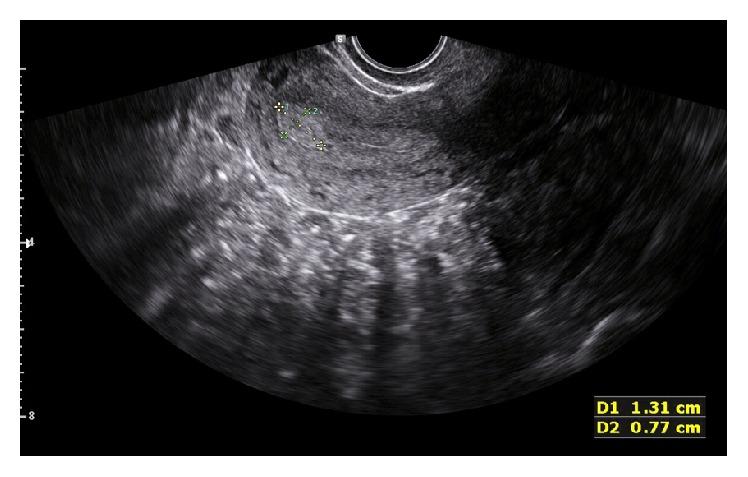

The aim is to compare hysteroscopy, two-dimensional transvaginal ultrasound (2D TVUS), and three-dimensional (3D) Virtual Organ Computer-aided AnaLysis™ (VOCAL) to detect endometrial polyps (EPs) in premenopausal women with abnormal uterine bleeding (AUB). This prospective study was done at Ain Shams Maternity Hospital, Egypt, from March 5, 2015, to December 30, 2015, enrolling 118 premenopausal women with AUB. 2D TVUS, 3D VOCAL, and hysteroscopy were done. 109 patients reached final analysis. 36 women (33%) were diagnosed with EP by 2D TVUS. 50 (45.9%) had EP by hysteroscopy. Endometrial thickness was 10.1 mm by 2D TVUS and endometrial volume was 4.92 mL by VOCAL in women with EP by hysteroscopy compared to 9.9 mm and 3.50 mL in women with no EP, respectively ( = 0.223; = 0.06). 2D TVUS has sensitivity, specificity, and positive and negative predictive values of 54%, 84.7%, 75%, and 68.5%, respectively. Endometrial thickness of >7.5 mm has sensitivity, specificity, positive and negative predictive values, and overall accuracy of 82%, 37.3%, 52.6%, 71%, and 57.8%, respectively. Endometrial volume of >1.2 mL has sensitivity, specificity, positive and negative predictive values, and overall accuracy of 90%, 42.4%, 57%, 83.3%, and 64.2%, respectively. 3D VOCAL may be used as a noninvasive method for the diagnosis of EP in premenopausal women with AUB.

目的是比较宫腔镜检查、二维经阴道超声(2D TVUS)和三维(3D)虚拟器官计算机辅助分析™(VOCAL)在诊断有异常子宫出血(AUB)的绝经前女性子宫内膜息肉(EP)方面的效果。这项前瞻性研究于2015年3月5日至2015年12月30日在埃及艾因·沙姆斯妇产医院进行,纳入了118名有AUB的绝经前女性。进行了2D TVUS、3D VOCAL和宫腔镜检查。109例患者进行了最终分析。36名女性(33%)经2D TVUS诊断为EP。50名(45.9%)经宫腔镜检查诊断为EP。经宫腔镜检查诊断为EP的女性,2D TVUS测得的子宫内膜厚度为10.1毫米,VOCAL测得的子宫内膜体积为4.92毫升,而未患EP的女性分别为9.9毫米和3.50毫升(P = 0.223;P = 0.06)。2D TVUS的敏感性、特异性、阳性和阴性预测值分别为54%、84.7%、75%和68.5%。子宫内膜厚度>7.5毫米时,敏感性、特异性、阳性和阴性预测值以及总体准确率分别为82%、37.3%、52.6%、71%和57.8%。子宫内膜体积>1.2毫升时,敏感性、特异性、阳性和阴性预测值以及总体准确率分别为90%、42.4%、57%、83.3%和64.2%。3D VOCAL可作为诊断有AUB的绝经前女性EP的一种非侵入性方法。